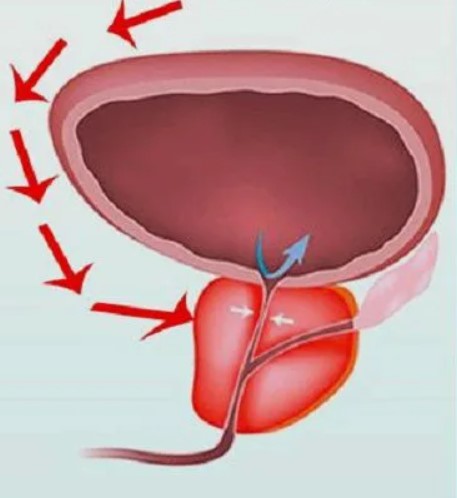

Kongestivní (městnavá) prostatitida je způsobena stagnací sekretu v prostatě a/nebo krve v žilách tohoto orgánu, což se nejčastěji vyskytuje v následujících případech:

Stagnující prostatitida se v důsledku infekce velmi rychle změní v bakteriální prostatitidu. Je známo, že v mnoha případech prostatitidě předchází nebo ji doprovází zánět prostaty v močové trubici (uretritida).

Pokud se jedná o zánětlivé onemocnění (nikoli bakteriální), je možné, že je narušeno prokrvení svalů obklopujících prostatu. Pro obnovení krevního oběhu neexistuje lepší a účinnější cvičení než dřepy. Pro začátek byste si měli udělat test a zkusit dřepovat s rovnýma rukama zvednutýma nad hlavu.